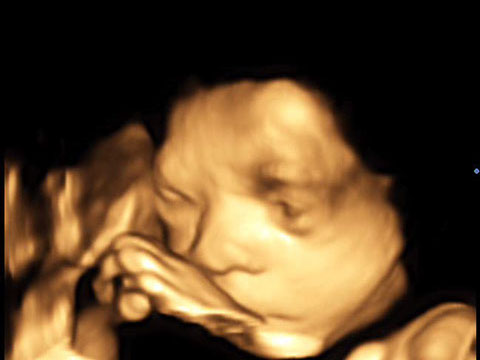

Der 4D-Ultraschall ist eine Methode der Ultraschall-Untersuchung, bei der das Ultraschallgerät ein dreidimensionales Bild des Untersuchungsobjekts in Echtzeit erzeugt.

Er dient in erster Linie der Erkennung einer Entwicklungsstörung, bzw. Fehlbildung des Kindes. 95% der Fehlbildungen bei Kindern können mittels moderner Ultraschall-Technologie heute bereits vor der Geburt erkannt werden.

Die 4D-Ultraschallsonographie hilft durch eine optimale Betreuung in der Schwangerschaft Schäden in Grenzen zu halten, bei bestimmten Problemen ist es sogar noch möglich, während der Schwangerschaft einzugreifen.

Er kann als risikofreie Untersuchungsmethode ohne nennenswerte Belastung für Mutter und Kind durchgeführt werden.